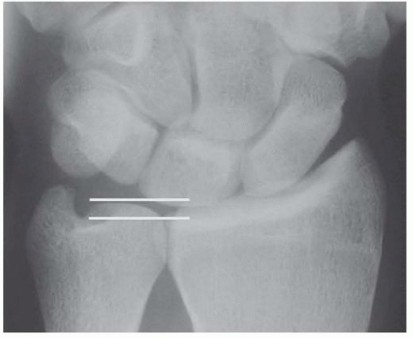

The radiographic evaluation begins with a high-quality, standardized wrist series. The most critical image is the Palmer 90/90 neutral rotation view. Because ulnar variance changes dynamically with forearm rotation—increasing in pronation and decreasing in supination—a standardized view is mandatory to prevent gross miscalculation. The patient is positioned with the shoulder abducted to 90 degrees, the elbow flexed to 90 degrees, and the forearm in absolute neutral rotation.

FIG 3 • A. Ulnar-plus variance unequivocally demonstrated on a standardized 90/90 neutral rotation PA view, confirming the mechanical basis for the patient's abutment syndrome.

On this view, we carefully scrutinize the proximal ulnar pole of the lunate and the radial aspect of the triquetrum for subchondral sclerosis or cystic changes, which are pathognomonic for chronic impaction. We then template the exact amount of ulnar shortening required. Our surgical objective is to achieve a final ulnar variance of minus 1 to minus 2 mm.